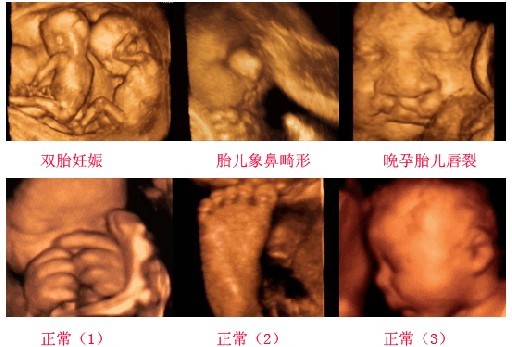

四维彩超能够检查出的疾病:

第二四维彩超可以坚持上述对疾病,还可以检查喝多大家未知的检查功能,具体如下,心脏,循环系统,胎儿颅内,脊柱等神经系统,颜面,手足,胎儿胃泡,肠道是否有梗阻等消化系统的异常,膀胱,输尿管,双肾等泌尿系统;

作为四维彩超好代表,杭州玛莉亚妇产医院开展了划时代阶段GE彩超检查,共设四个检查时间,其中孕23-27周就是第三阶段,主要目的是胎儿医学排畸。而第一阶段孕5-10周做GE彩超主要是检查孕囊大小、羊水、胎心等发育情况,同时清晰地看到胚囊及胚芽。第二阶段孕11-14周主要是检查胎儿现阶段各项发育指标,并拍摄胎儿整理成像及轮廓。第四阶段孕28-32周主要是检查胎儿成熟度,清晰地看到胎儿接近出生时的模样。